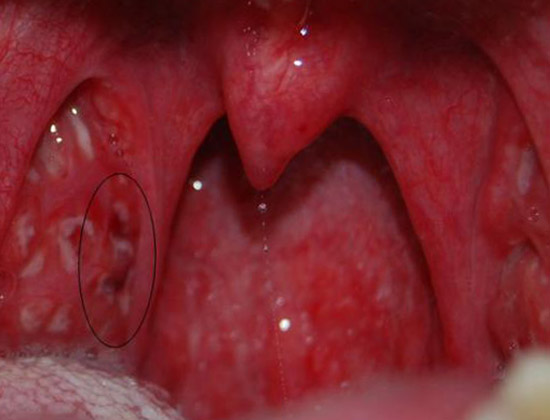

- При хроническом тонзиллите скопившийся гной в лакунах может быть жидким или густым. При осмотре можно обнаружить гнойные пробки в лакунах. Наличие гноя в лакунах является причиной неприятного гнилостного запаха изо рта, что является важным признаком хронического тонзиллита.

Наличие гноя в лакунах и повторяющиеся случаи ангины в течение года, сопровождающиеся симптомами токсикоза, являются надежными признаками хронического тонзиллита, обладающими высокой достоверностью.

На изображении представлен хронический тонзиллит. Присутствуют основные признаки заболевания, в лакунах наблюдается гной и гнойные пробки.